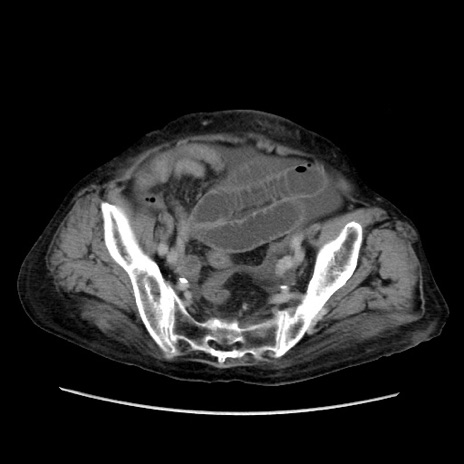

症例31(横断像)

【症例】80歳代 女性

【主訴】腹部膨満感

【現病歴】他院にて肝硬変にてフォロー中。1週間前から便秘、腹部膨満感、臍部腫瘤あり受診となる。

【既往歴】肝硬変

【身体所見】腹部膨隆あり、皮膚変化なし、疼痛なし。

【データ】WBC 4600、CRP 0.25